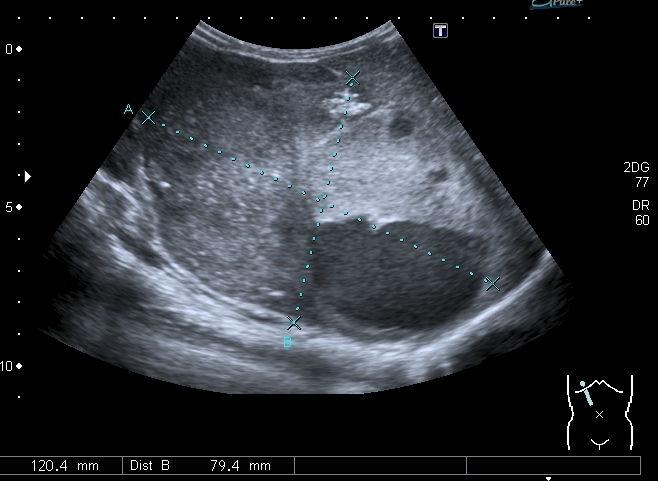

При УЗИ вся правая половина живота выполнена солидно - кистозным образованием больших размеров.

Правая почка нашлась в полости таза, верхним полюсом прилежала к образованию, но не была с ним связана.